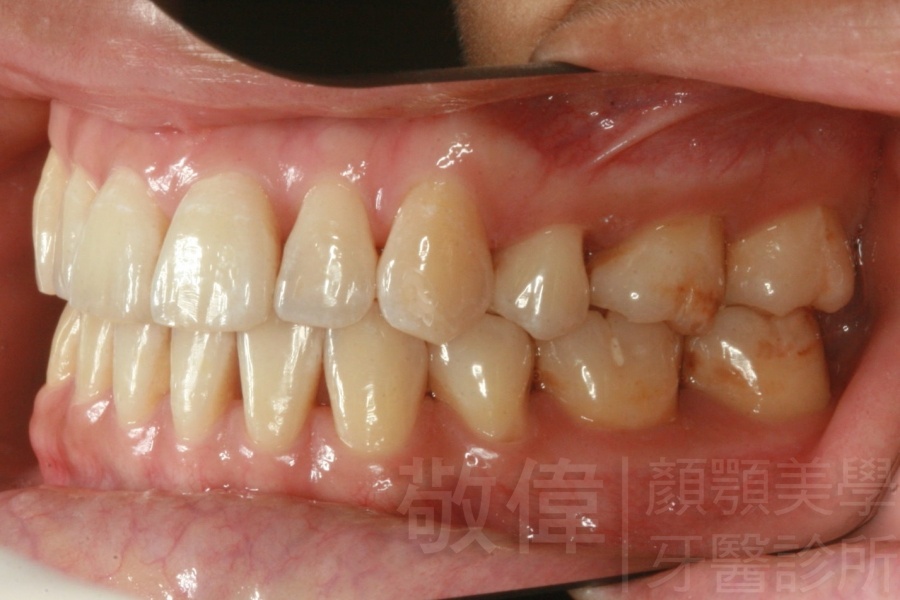

齒顏矯正/戽斗、亂牙、爛牙,變身 免植牙的健牙美女

<個案說明>

變臉矯正,原來戽斗妹跟大歪臉變成自信正妹

經由本院3D數影X光影像儀分析、與3D齒顎顏矯正技術,再配合口腔顎面正顎專科醫師施以正顎手術治療,雙方共同合作,使患者臉部外觀有很好的改善,大歪變小歪,產生了天南地北的大改變,她的人生也整個變得不一樣。

因為矯正與正顎手術的配合,使「戽斗妹」變成了「陽光正妹」,完全的改變了她的人生,在面對各種場合、與人交際都散發出自信微笑。所以,奉勸家長,如果小朋友有臉顎畸型的問題,應該考慮配合做這種簡單、安全、有效的正顎手術。